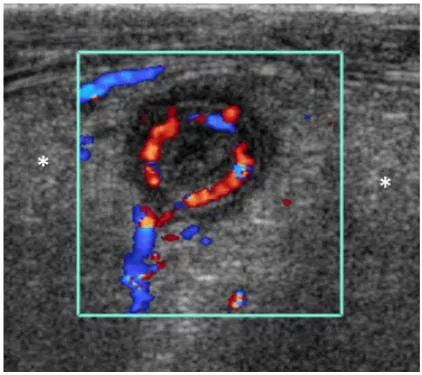

Hyperemia

Hyperemia는 염증의 중요한 지표

염증있는 appendix wall은 color doppler에서 hypremic 하다

민감도 52%, 특이도 96%